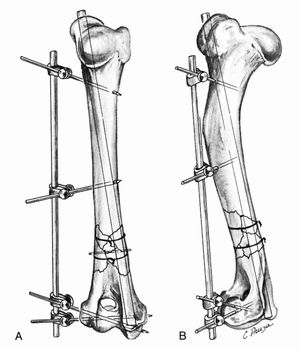

圧迫プレートは、AOグループまたはASIFグループの考案した圧迫装置を使って装着する場合と、圧迫装置を使うことなく、すべり孔を設けたK-U式圧迫プレートを装着して目的を達成する場合とがあります。

前者では、圧迫装置で骨片を動かして断端を密着させ、後者では、すべり孔をネジが滑動することによって、断端を密着させます。

プレートを固定するネジは、それぞれの骨片に2個以上挿入する必要があります。